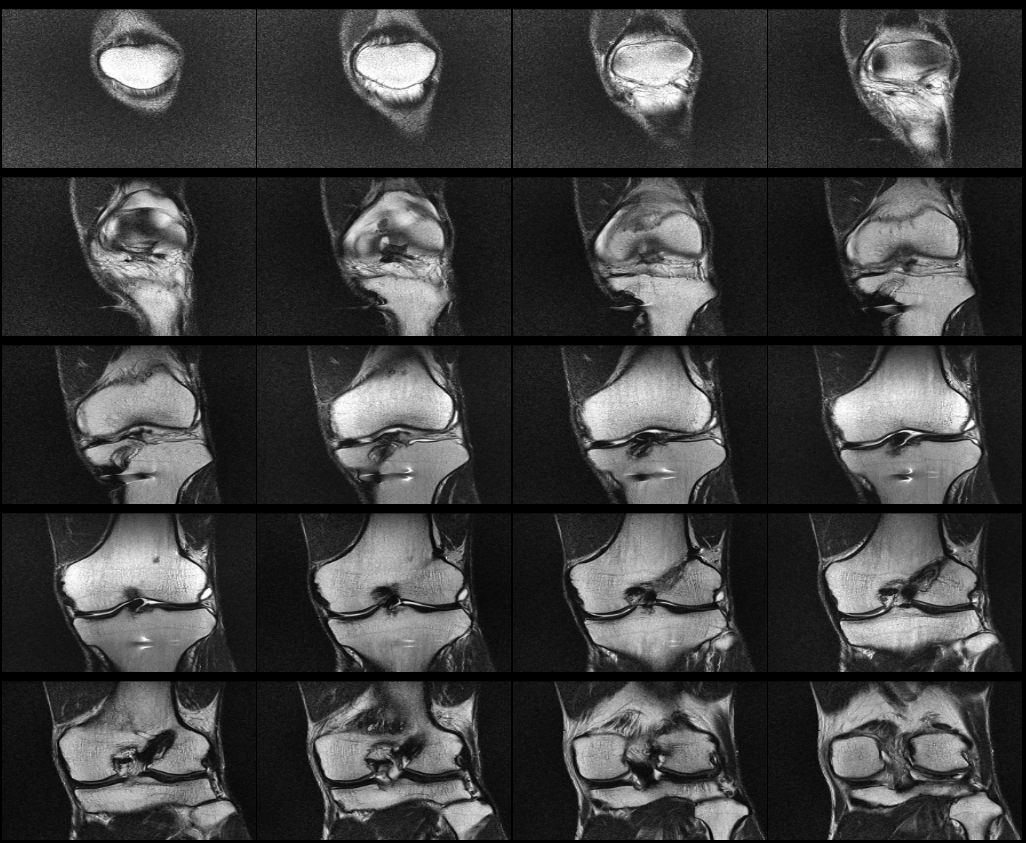

무릎 십자인대 재건술 후 약8년이 지난 지금 mri를 찍었습니다. 판독부탁드립니다ㅠㅠ

약 8년전 무릎 전방십자인대 재건술을 했는데 , 운동관련 직종이다 보니 , 운동을 많이 합니다.

최근들어 무릎에 불편한 통증이 있어 mri를 찍었는데 ,

활막염이라는 말만 들었는데 , 여러 선생님들의 의견을 듣고 싶어 사진올립니다. 판독해주시면 정말 너무너무

안녕하세요. 채홍석 의사입니다. MRI 퀄리티가 나빠서 판독은 어렵겠네요.